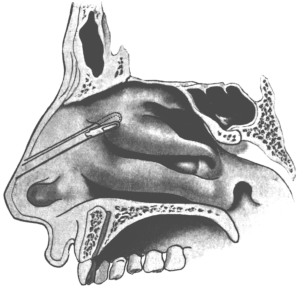

| 345. | Catheterizing the Sphenoidal Sinus | 654 |

| 347. | Radiograph showing a Probe in the Sphenoidal Sinus | 657 |